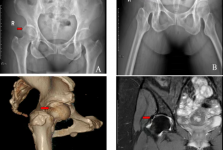

运动医学(Sports Medicine)是研究运动系统相关疾病的学科,主要运用先进的医学理论和微创技术,治疗骨关节、肌腱、韧带、软骨等运动系统急、慢性损伤,并给予科学的康复指导,最大程度的恢复肢体功能。我院运动医学科作为山东省青岛体育... 查看更多